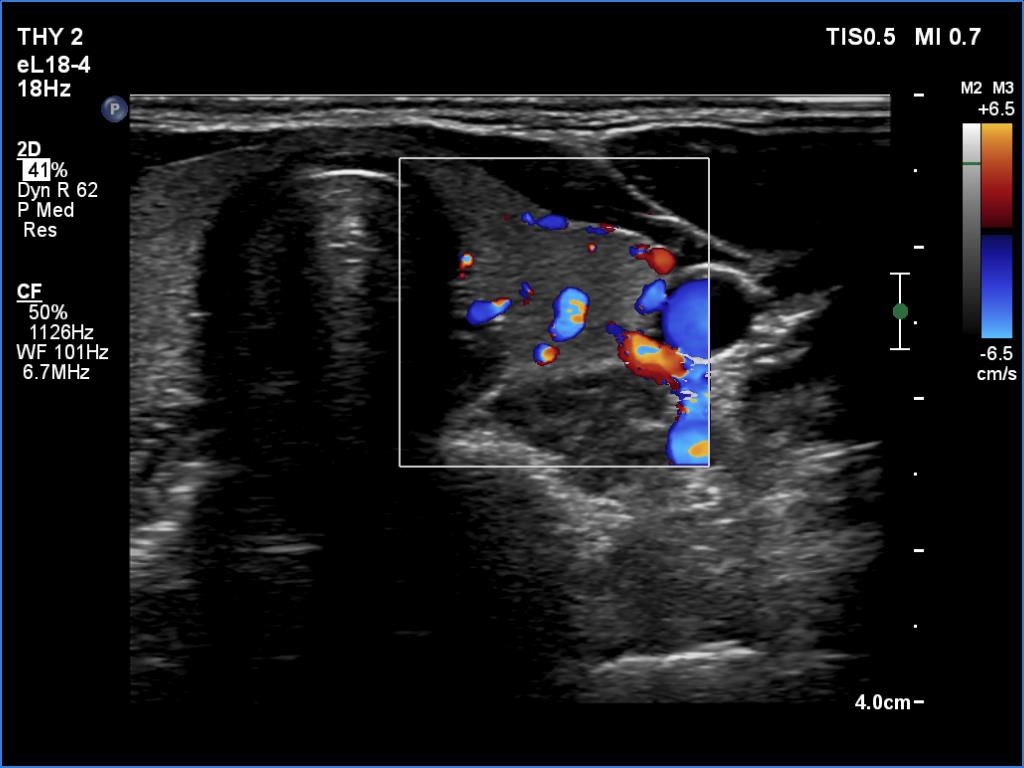

Left lobe, transverse view, color Doppler mode. The vascularity is average.